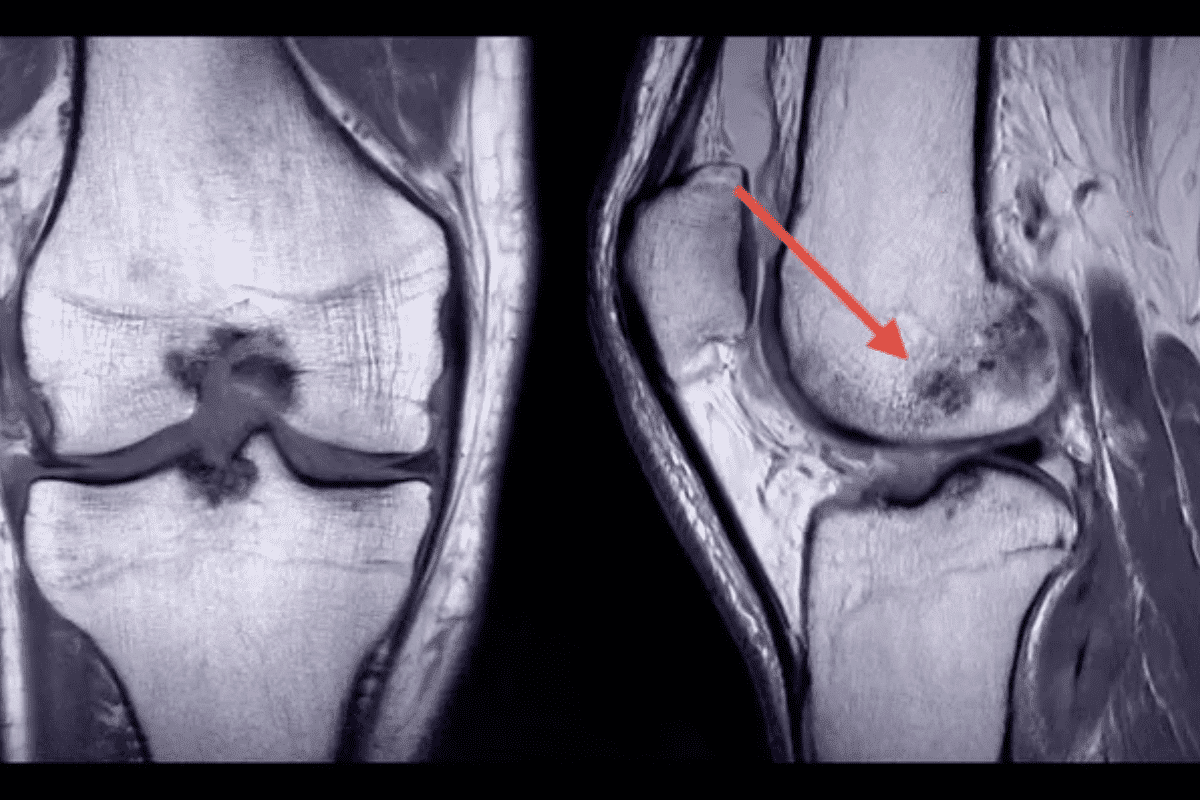

Hot Spots vs. Cold Spots: What They Mean

Bone scans highlight areas of high or low bone activity. Hot spots show where the bone is working too hard, often due to cancer, fractures, or infections. Cold spots indicate where the bone is not working well, like in some cancers or dead bone tissue.

How Cancer Appears on Bone Scans

Cancer shows up as “hot spots” on bone scans. These spots mean the bone is repairing more than usual. This can mean cancer is present.

Key characteristics of cancer on bone scans include:

Arthritis Signatures on Bone Scans

Arthritis changes bone activity, making bone scans useful. They show “hot spots” where bone activity is high. These spots tell doctors how bad the arthritis is.

The hot spots’ pattern varies by arthritis type. Osteoarthritis hits specific joints like hips and knees. Rheumatoid arthritis affects many joints on both sides.

Osteoarthritis vs. Rheumatoid Arthritis Appearances

Osteoarthritis shows up in specific joints on scans. Rheumatoid arthritis looks more widespread and symmetrical. Knowing this helps doctors tell these arthritis types apart.